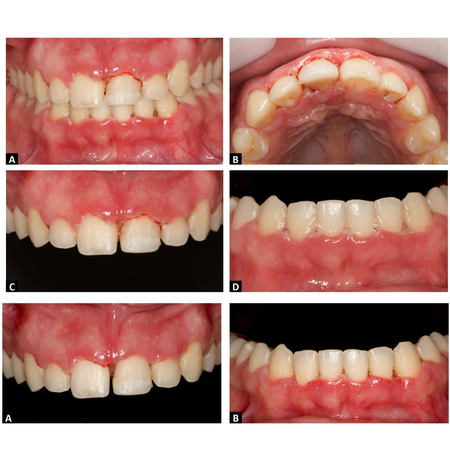

OBJETIVO: O objetivo do presente estudo foi descrever a conduta terapêutica inicial e de manutenção de uma paciente com um quadro clínico de gengivite necrosante. RELATO DE CASO: Paciente leucoderma, sexo feminino, 20 anos de idade, sem problemas sistêmicos, revelou queixa de dor e sangramento gengival à escovação. Ao exame clínico, verificou-se acúmulo de biofilme em todas as faces dentárias, com papilas interdentais e margem gengival recobertas por epitélio necrótico com...

OBJECTIVE: To describe the initial and maintenance treatments of a patient with clinical manifestation of necrotizing gingivitis. CASE REPORT: A 20-year-old Caucasoid female patient, without systemic problems, complained of pain and gingival bleeding upon brushing. Clinical examination revealed biofilm accumulation on all tooth surfaces, with interdental papillae and gingival margins covered by necrotic epithelium with hemorrhagic areas and intense inflammatory process in both arches....